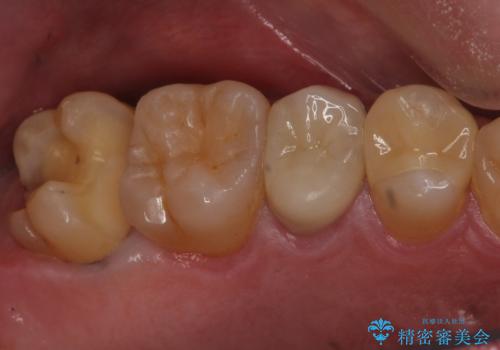

放置していた虫歯 セラミックインレーによる治療

- 食事の際に右上の奥歯が痛むので診てほしいとのことで来院。

視診では明らかに食べ物が詰まっているのがわかり、レントゲン写真では大きな虫歯の像が確認されました。

虫歯の大きさ次第でクラウンかインレーのどちらかになるだろうとご説明させていただき、今回はセラミックインレーでの治療となりました。